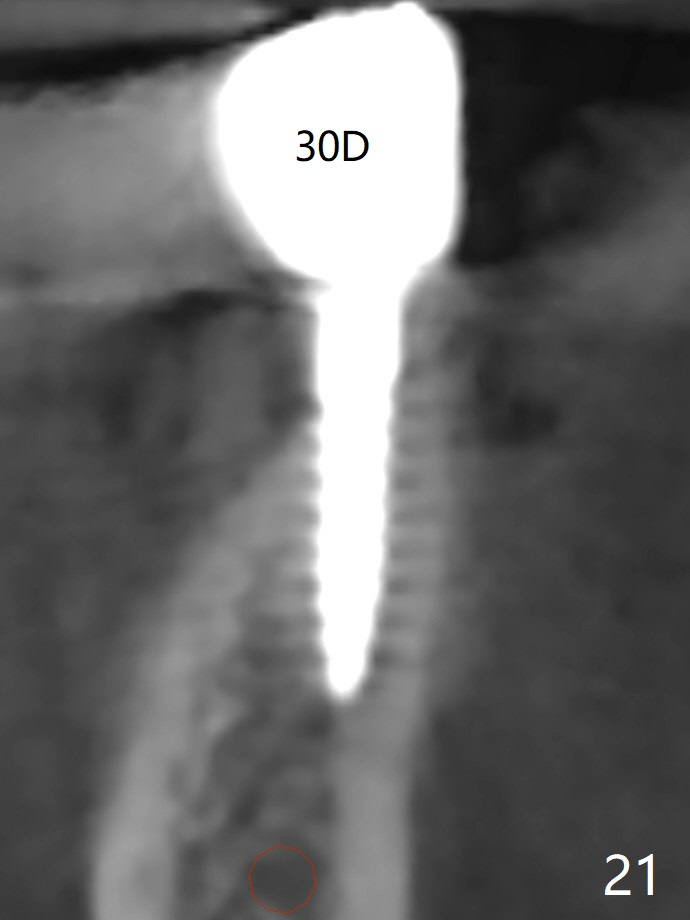

The edentulous ridge at #30 is narrow (Fig.1). After ridge reduction, osteotomy is initiated with 1.2 mm drill for 10 mm; the mesial osteotomy is to be changed (Fig.2 red line). Using a 1.2 mm drill placed in the distal osteotomy (Fig.3 D), the mesial osteotomy changes in trajectory with subsequent placement of a 2.5x10(4) mm 1-piece implant. Since the mesial implant is high in occlusion, the cuff of the distal implant is changed to be 2 mm (Fig.4 (shorter black line)). Panoramic X-ray is taken to show no violation of the Inferior Alveolar Canal (Fig.5 red dashed line). These two 1-piece implants are slightly lingually placed (Fig.6). The crestal bone around the implants resorbs without thread exposure 5 months postop (Fig.7). Impression is taken for a splinted crown (Fig.8-12). There is no metal show around the 2.5 mm 1-piece implants 6 months postop (advantage) vs. that at #28 and 29 (Fig.13). Bitewing is taken post cementation to determine whether residual cement is present (Fig.14). There is periodic swelling and pain in the lower right quadrant 2 years post cementation (Fig.15). In fact periimplantitis appears to have developed at #28 (Fig.16) with loss of the buccal bone (Fig.17,18). The buccal bone loss is less at #29 (Fig.19) and #20 (Fig.23) and no at #30 mesial and distal implants (Fig.20,21). A much smaller implant will be placed lingually at #28 immediate (Fig.24,25).